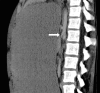

Background: Superior mesenteric artery (SMA) syndrome is an uncommon condition resulting in partial small bowel obstruction because of external compression of the third portion of the duodenum between the SMA anteriorly and the aorta posteriorly. SMA syndrome often presents with postprandial nausea, bilious vomiting, and abdominal pain with associated weight loss. Onset of symptoms can be acute (occurring in the setting of rapid weight loss because of trauma/surgery) or can be vague and chronic over many years.

Case reports: We present two cases of female adolescents who presented with symptoms of duodenal obstruction attributed to SMA syndrome. Both failed conservative treatment with weight gain and underwent successful laparoscopic duodenojejunostomy procedures with resolution of duodenal obstruction.

Conclusion: In the differential diagnosis of persistent nausea and bilious vomiting, even in the setting of an eating disorder, SMA syndrome should be considered. Upper gastrointestinal examination is the primary modality for diagnosing SMA syndrome, but ultrasound is an inexpensive, rapid screening tool for patients with unexplained abdominal pain. Abdominal computed tomography may also be helpful in selected patients. Conservative therapy consisting of nutritional support to enhance weight gain is usually sufficient and is accomplished with placement of a nasojejunal feeding tube past the point of duodenal compression. When conservative therapy fails, laparoscopic duodenojejunostomy can provide definitive relief of the obstruction.